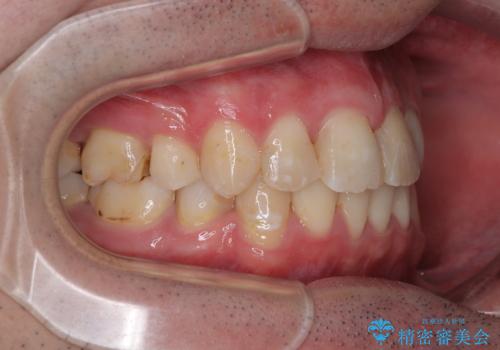

2年半の治療期間を想定しており、予定通りの期間で無事に終了することができました。

唇や顎先に力を入れないなくてもスムーズに唇を閉じることができるようになりました。